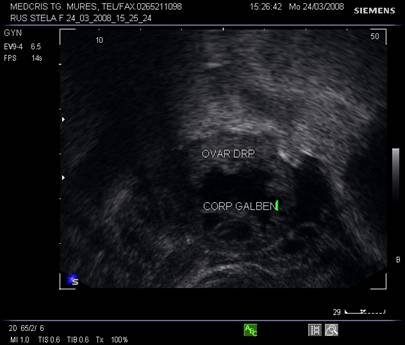

Fig. Nr.373. Corp galben recent, ziua a XV a de ciclu menstrual , prima zi postovulator. Se remarca aspectul ratatinat, anecogenitatea interna asociata cu fine puncte avand ecogenitate medie .( ecografie transvaginala )

Ovarele. Sectiunea longitudinala directa, spre peretele lateral pelvin, la ecografia transvaginala, pune in evidenta ovarele cu forma elipsoidala. Acestea au structura ecografica relativ slab ecogena, in apropierea si sub vasele iliace.[5]

La pacientele care nu consuma contraceptive hormonale orale se pot identifica usor foliculii selectati preovulator sau corpul galben.

Semnele ecografice postovulatorii [2,6,9]

Ovarul

foliculul nu se mai observa in tensiune

foliculul colabat

aparitia corpului luteal

vascularizatie crescuta periferica la ecoDoppler